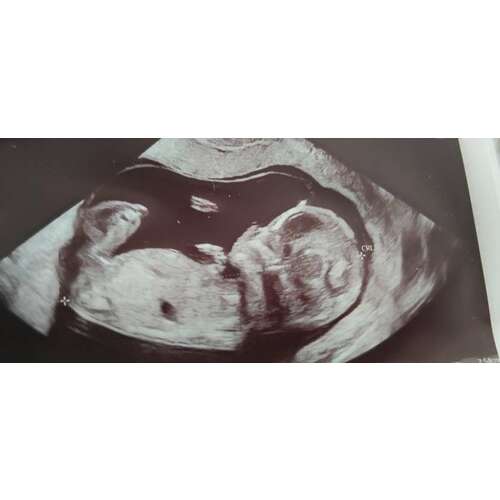

Daar zie je precies een piemeltje en een balletje, is mijn echo, weet ook nog niet 100% zeker maar dat maken ze mij wijs Hahaha 😅🙈

Staat inderdaad ook omhoog, dus een jongen!

Echt overduidelijk een jongen hoor haha! Onwijs leukkk❤️😍